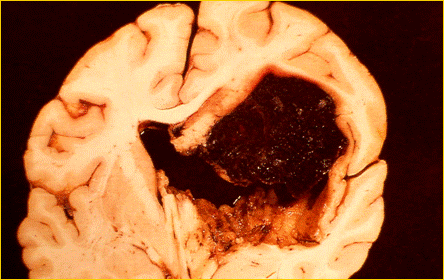

Le patologie che possono portare alla morte cerebrale sono l'emorragia cerebrale da rottura di un vaso intracranico, i traumi cranici ( incidenti stradali, ferite da proiettile ), le neoplasie cerebrali primitive.

REPERTO ANATOMICO DI MASSIVA EMORRAGIA CEREBRALE